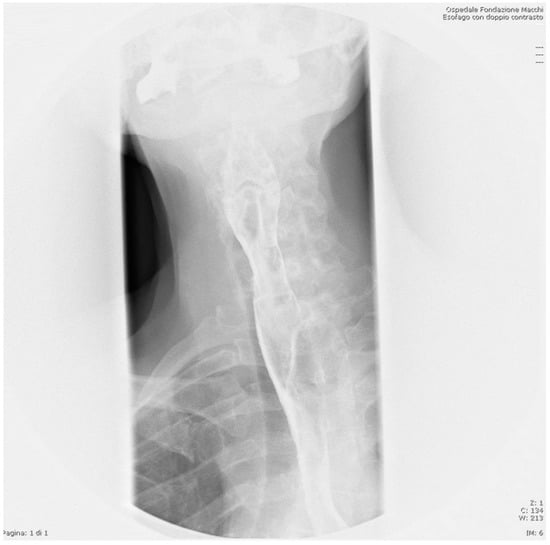

2. Case Presentation